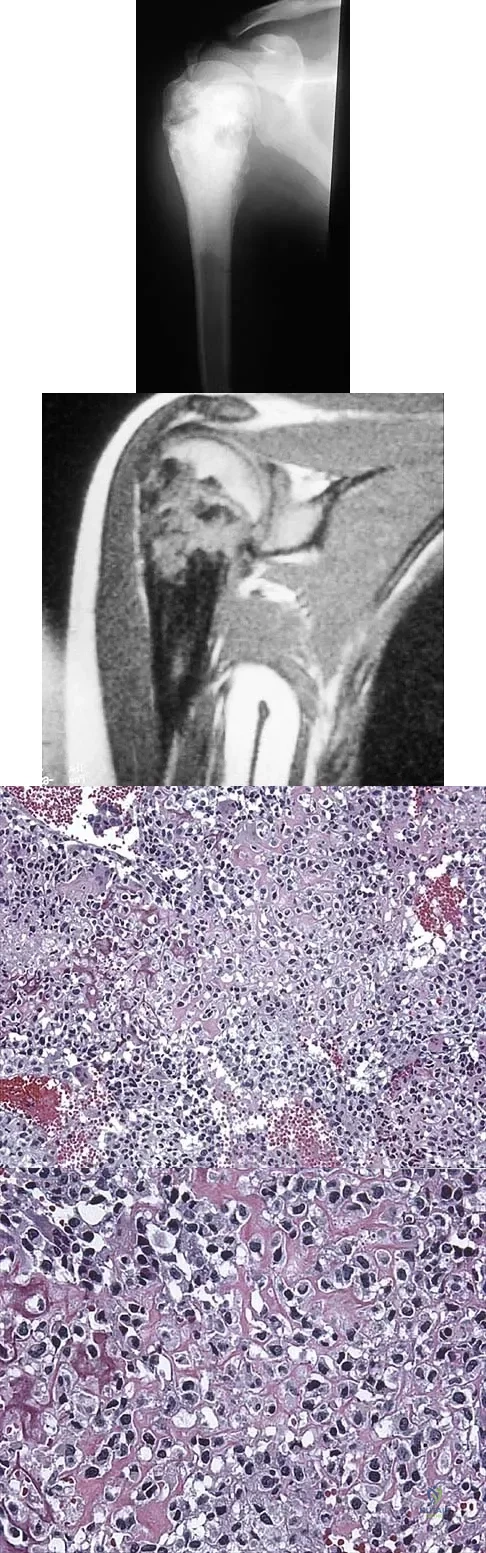

A 16-year-old girl has had pain in the left groin for the past 4 months. She notes that the pain is worse at night; however, she denies any history of trauma and has no constitutional symptoms. There is no history of steroid or alcohol use. Examination reveals pain in the left groin with rotation of the hip. There is no associated soft-tissue mass. A radiograph and MRI scan are shown in Figures 32a and 32b, and biopsy specimens are shown in Figures 32c and 32d. What is the most likely diagnosis?

Explanation

A 13-year-old girl has had a firm mass and pain in her right shoulder for the past several weeks. She denies any history of trauma. A radiograph and MRI scan are shown in Figures 31a and 31b. Biopsy specimens are shown in Figures 31c and 31d. What is the most likely diagnosis?

Explanation